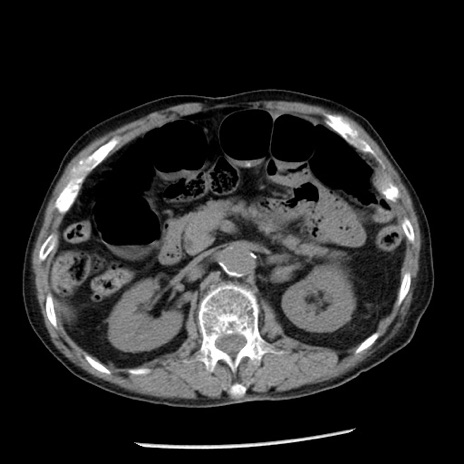

症例26(横断像)

【症例】80歳代男性

【主訴】嘔吐

【現病歴】昨晩2回嘔吐あり、今朝になっても嘔吐あり。来院。

【既往歴】胃潰瘍

【身体所見】意識清明、BT 37.6℃、BP 166/95mmHg、HR 100bpm、SpO2 97%、腹部:平坦・軟、腸蠕動音聴取良好、圧痛なし。

【データ】WBC 21900、CRP 1.46